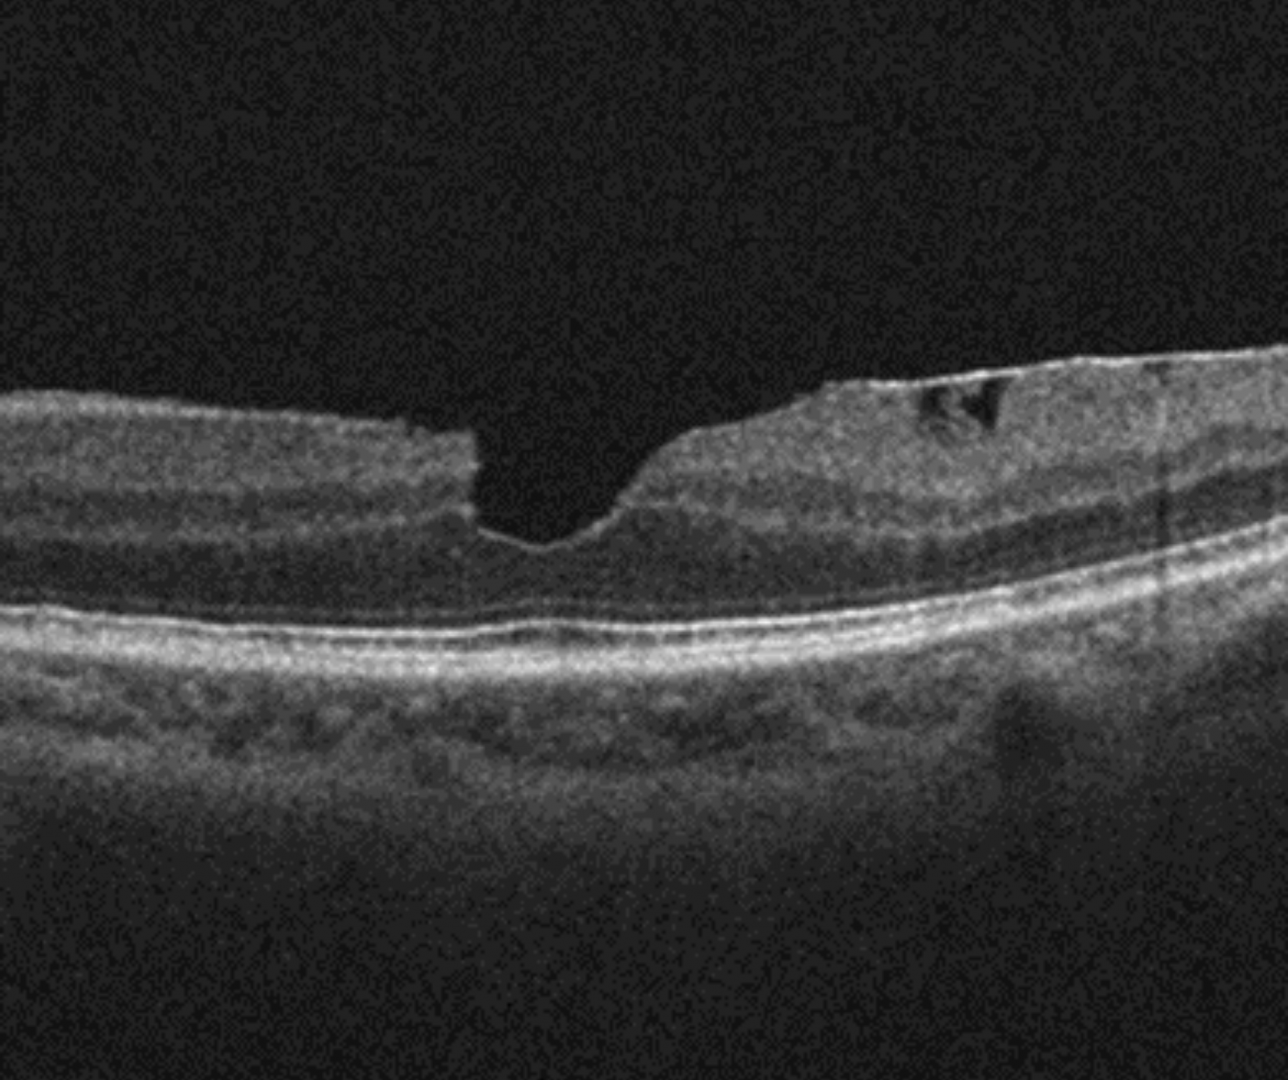

On OCT, a macular pseudohole is defined by three characteristics: the presence of a verticalized or steepened foveal profile, retinal thickening and an ERM sparing the foveal centre.